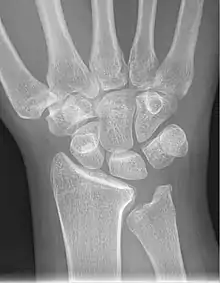

Shown is the right hand, palm down (left) and palm up (right).

Proximal: A=Scaphoid, B=Lunate, C=Triquetral, D=Pisiform

Distal: E=Trapezium, F=Trapezoid, G=Capitate, H=Hamate